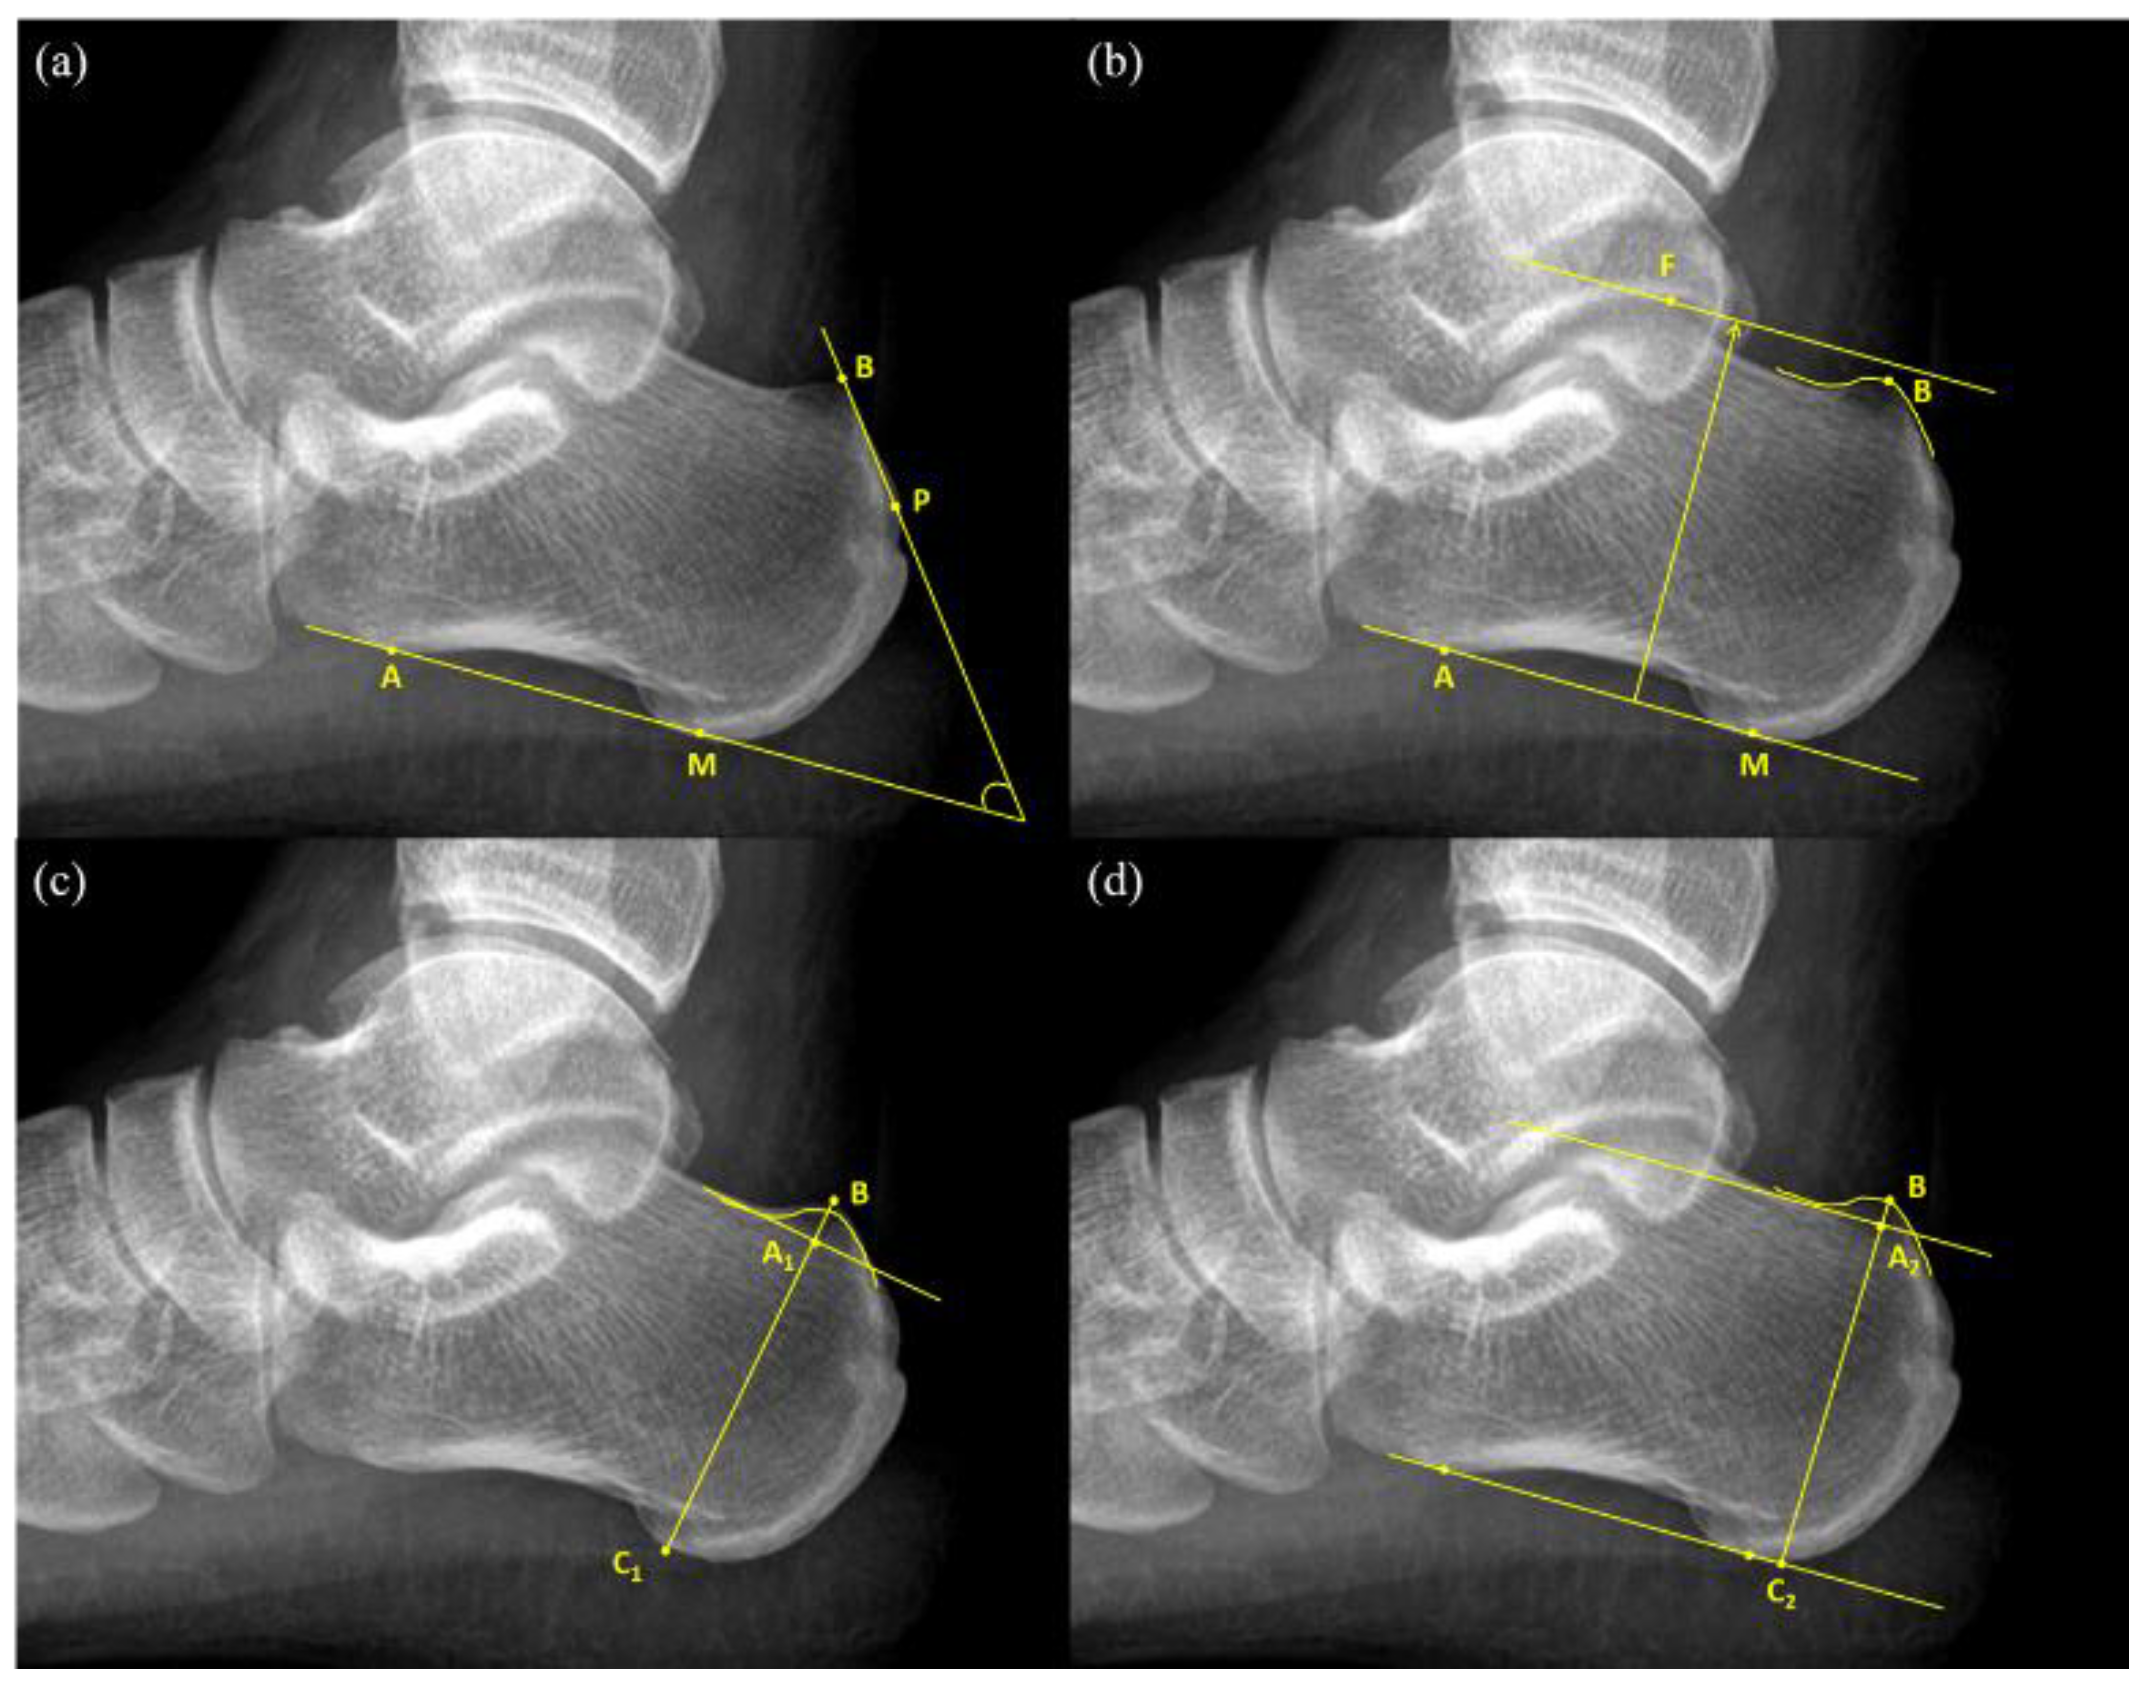

An FPA is the angle between the tangent line to the rear edge of the greater tuberosity of the calcaneal and the line connecting the anterior tubercle and medial tuberosity of the calcaneal (Figure 1a). The normal values of FPA range from 44° to 69°, and values greater than 75° are considered indicators of pathological changes [9].

Figure 1.

Radiographic measurement of Haglund’s deformity (a) Fowler-Philip angle = Angle between and (b) Heneghan-Pavlov parallel pitch lines; (c) Haglund’s height = ; Haglund’s height ratio = ; (d) Bump height = ; bump-calcaneus ratio = .

Heneghan–Pavlov PPL is the baseline formed by the line connecting the anterior tubercle and medial tuberosity of the calcaneus and a parallel superior line passing through the superior aspect of the talar articulation (Figure 1b). If PPL passes through the prominence of the posterosuperior edge of the calcaneal tuberosity, it is considered positive [10].

Haglund’s deformity height () (Figure 1c) was obtained first by drawing a reference line at the base of the posterosuperior calcaneal prominence and then by measuring the vertical distance between the vertex of the bump and the reference line [13]. Next, calcaneal height () was measured as the vertical distance between the vertex of the bump and the reference line drawn tangent to the lower edge of the calcaneus. Haglund’s height ratio was calculated as the ratio of Haglund’s deformity height to calcaneal height () (Figure 1c).

This study put forward two novel measurement methods for the diagnosis of Haglund’s deformity, namely bump height and bump-calcaneus ratio. Firstly, the baseline tangent to the anterior tubercle and medial tuberosity of the calcaneus was drawn. The baseline was moved upward parallelly until it touched the superior edge of the calcaneus, which was considered the reference line for bump height different to that in Haglund’s deformity height. Then, the reference line was moved upward parallelly again until it reached the superior edge of the bump and the intersection point was considered as the vertex of the bump (point B). The vertical distance between the vertex of the bump and the reference line was measured as bump height (), whereas the vertical distance between the vertex of the bump and the baseline was measured as calcaneal thickness (). Then, bump-calcaneus ratio was calculated by dividing bump height () by calcaneal thickness () (Figure 1d).